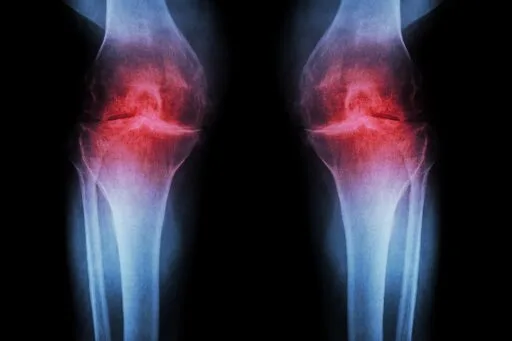

Anti-Aging Injection Regrows Knee Cartilage and Prevents Arthritis

In mice (of course) and human tissue exvivo. Earlier phase 1 studies with 15-PGDH has shown that it is safe and active in healthy volunteers.